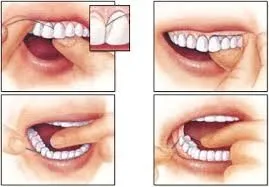

Floss at least once a day